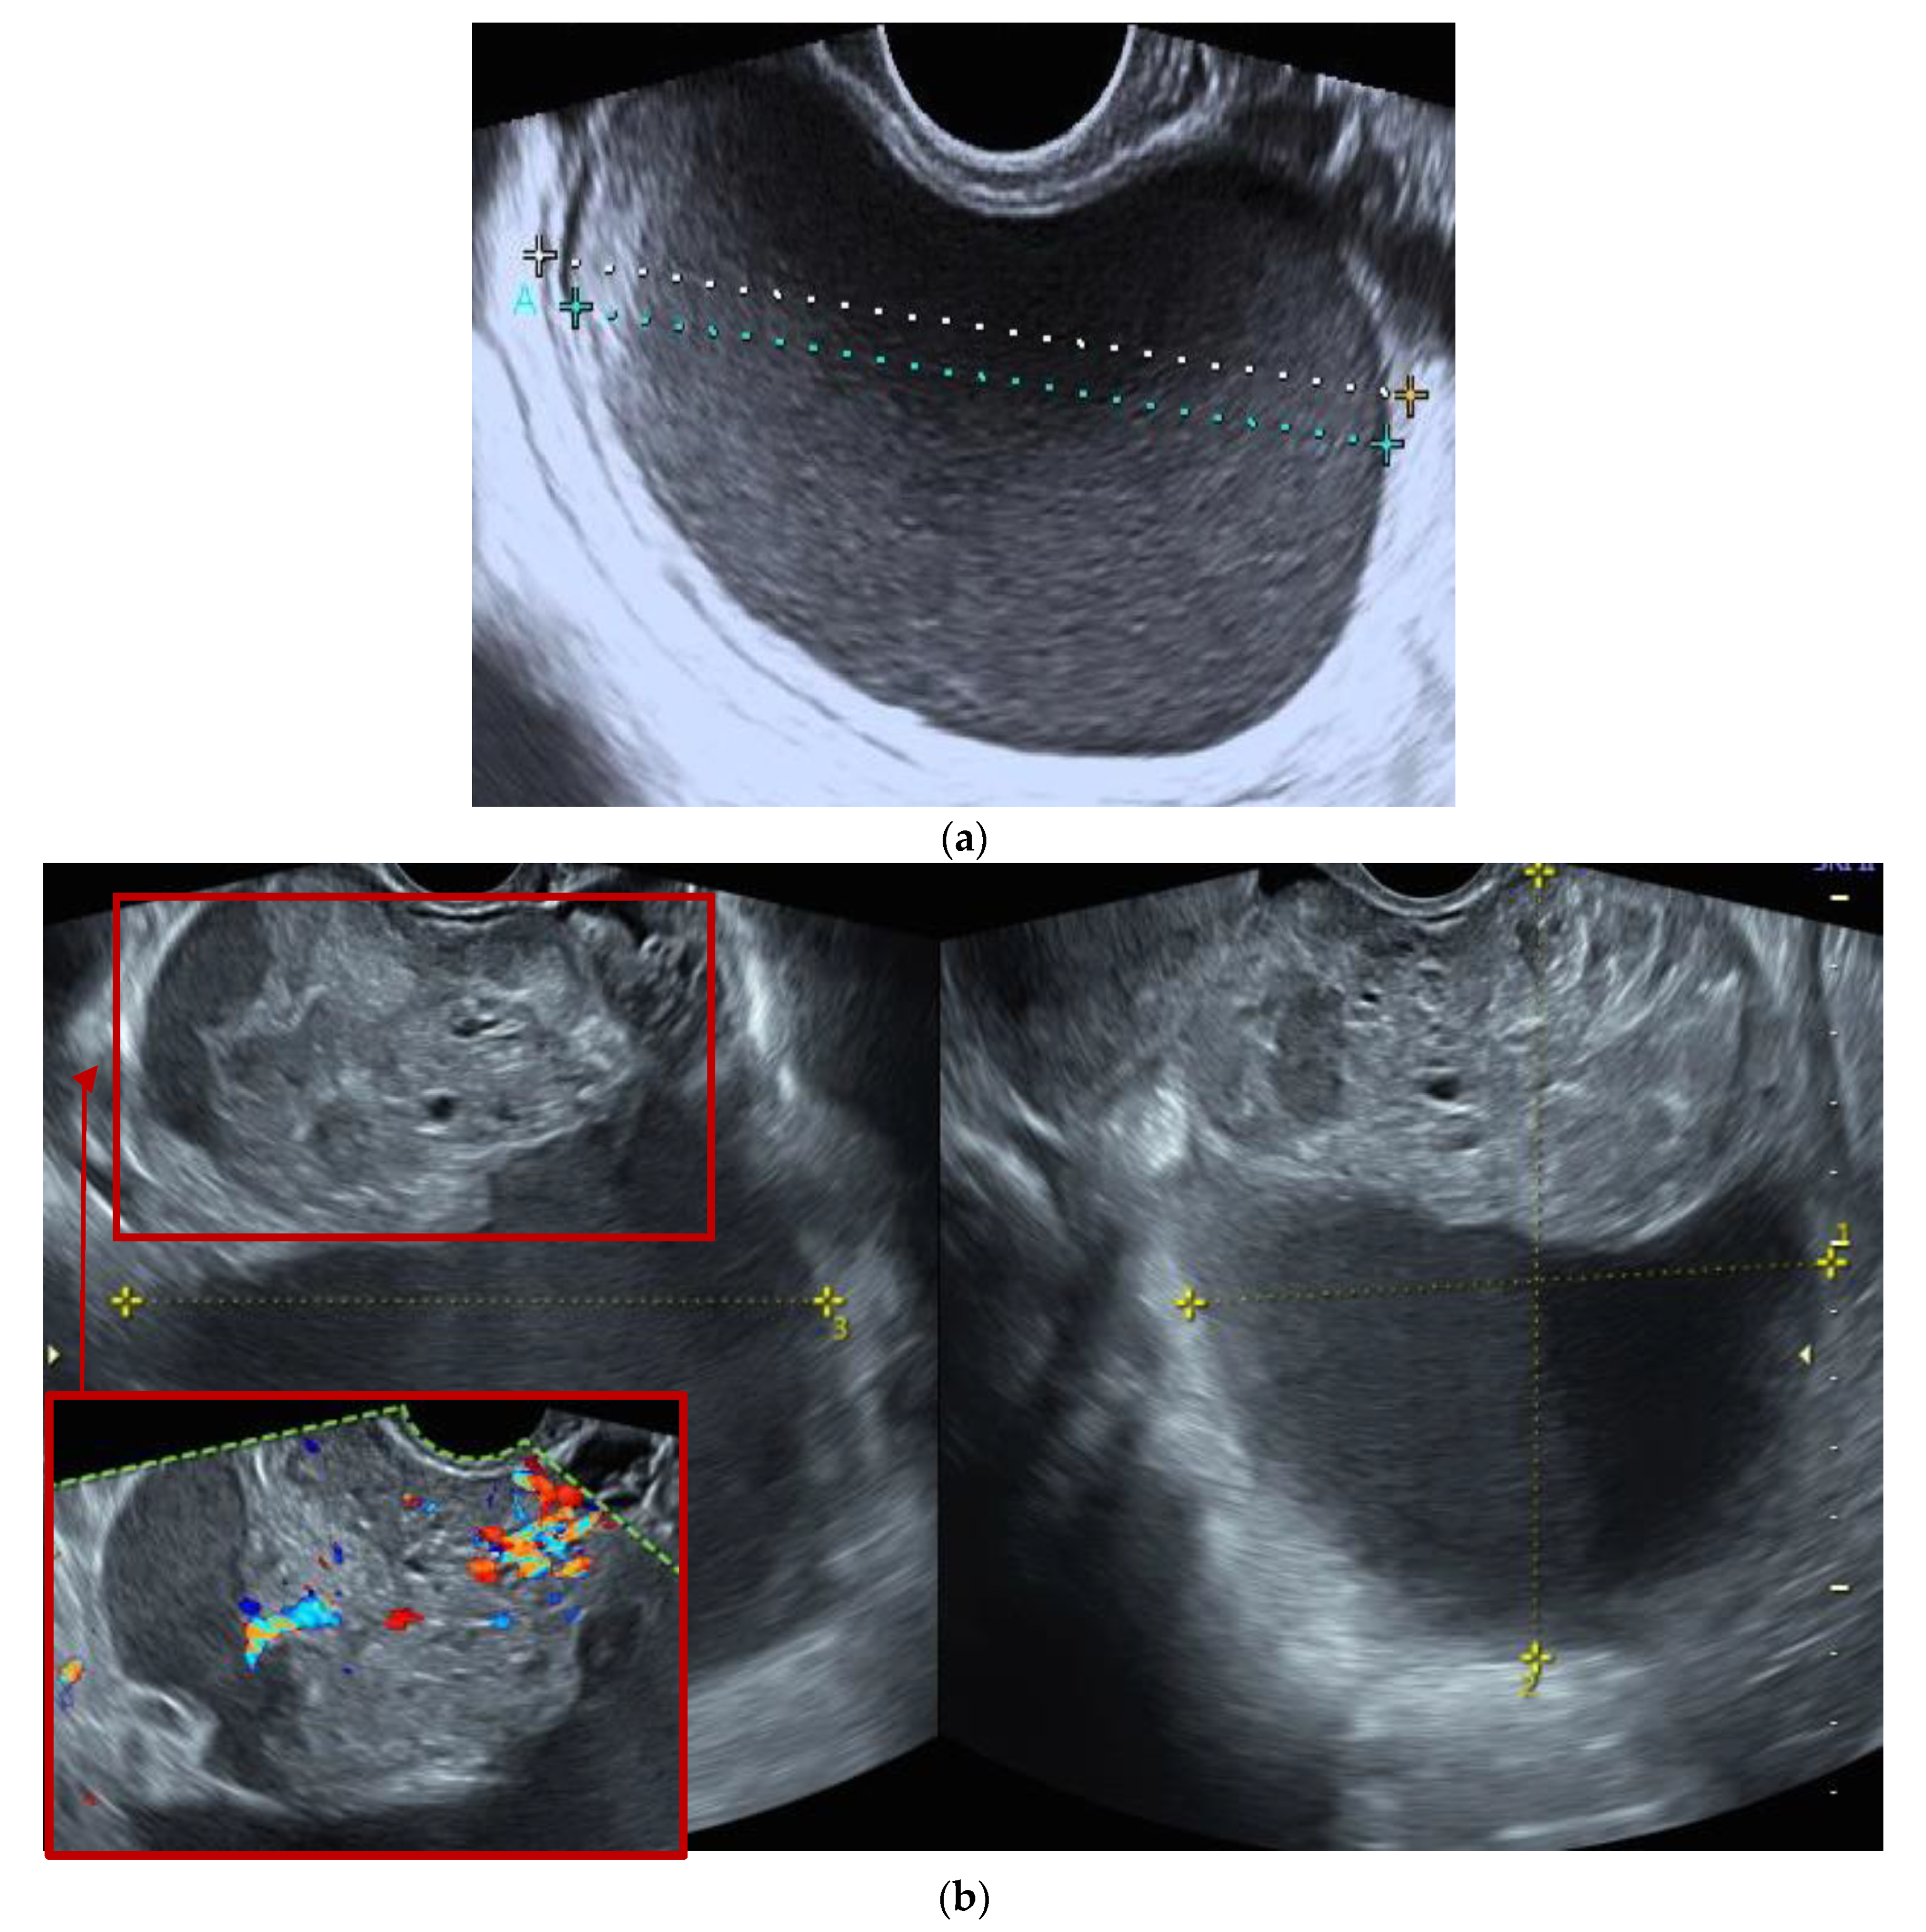

Figure 3.

Ultrasound features of an ovarian mucinous carcinoma (FIGO IA stage) initially classified as a benign lesion. (a), Unilocular ovarian formation with “ground glass” content and color score 1 with 72 × 69 × 46 mm, observed in an asymptomatic pre-menopausal woman (age: 46 years), classified as benign by the IOTA ADNEX model and labeled as a possible endometrioma. (b) The same lesion with increased sonographic morphological complexity observed at the 2nd evaluation, 3 months after the initial diagnosis (multilocular—solid tumor with color score 3, CA-125 46 U/mL), associated with persistent pelvic pain referred by the patient as moderate with two weeks duration.